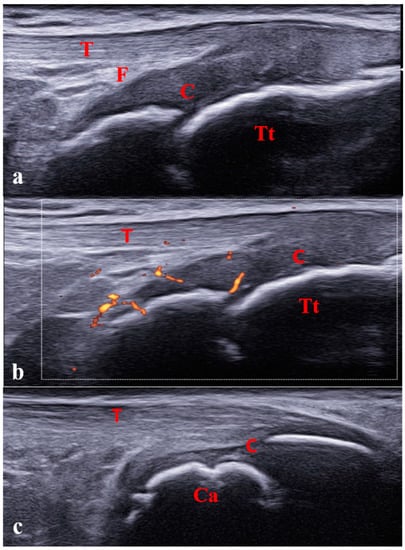

- Young, C.M.; Horst, D.M.; Murakami, J.W.; Shiels, W.E. Ultrasound-Guided Corticosteroid Injection of the Subtalar Joint for Treatment of Juvenile Idiopathic Arthritis. Pediatr. Radiol. 2015, 45, 1212–1217. [Google Scholar] [CrossRef] [PubMed]